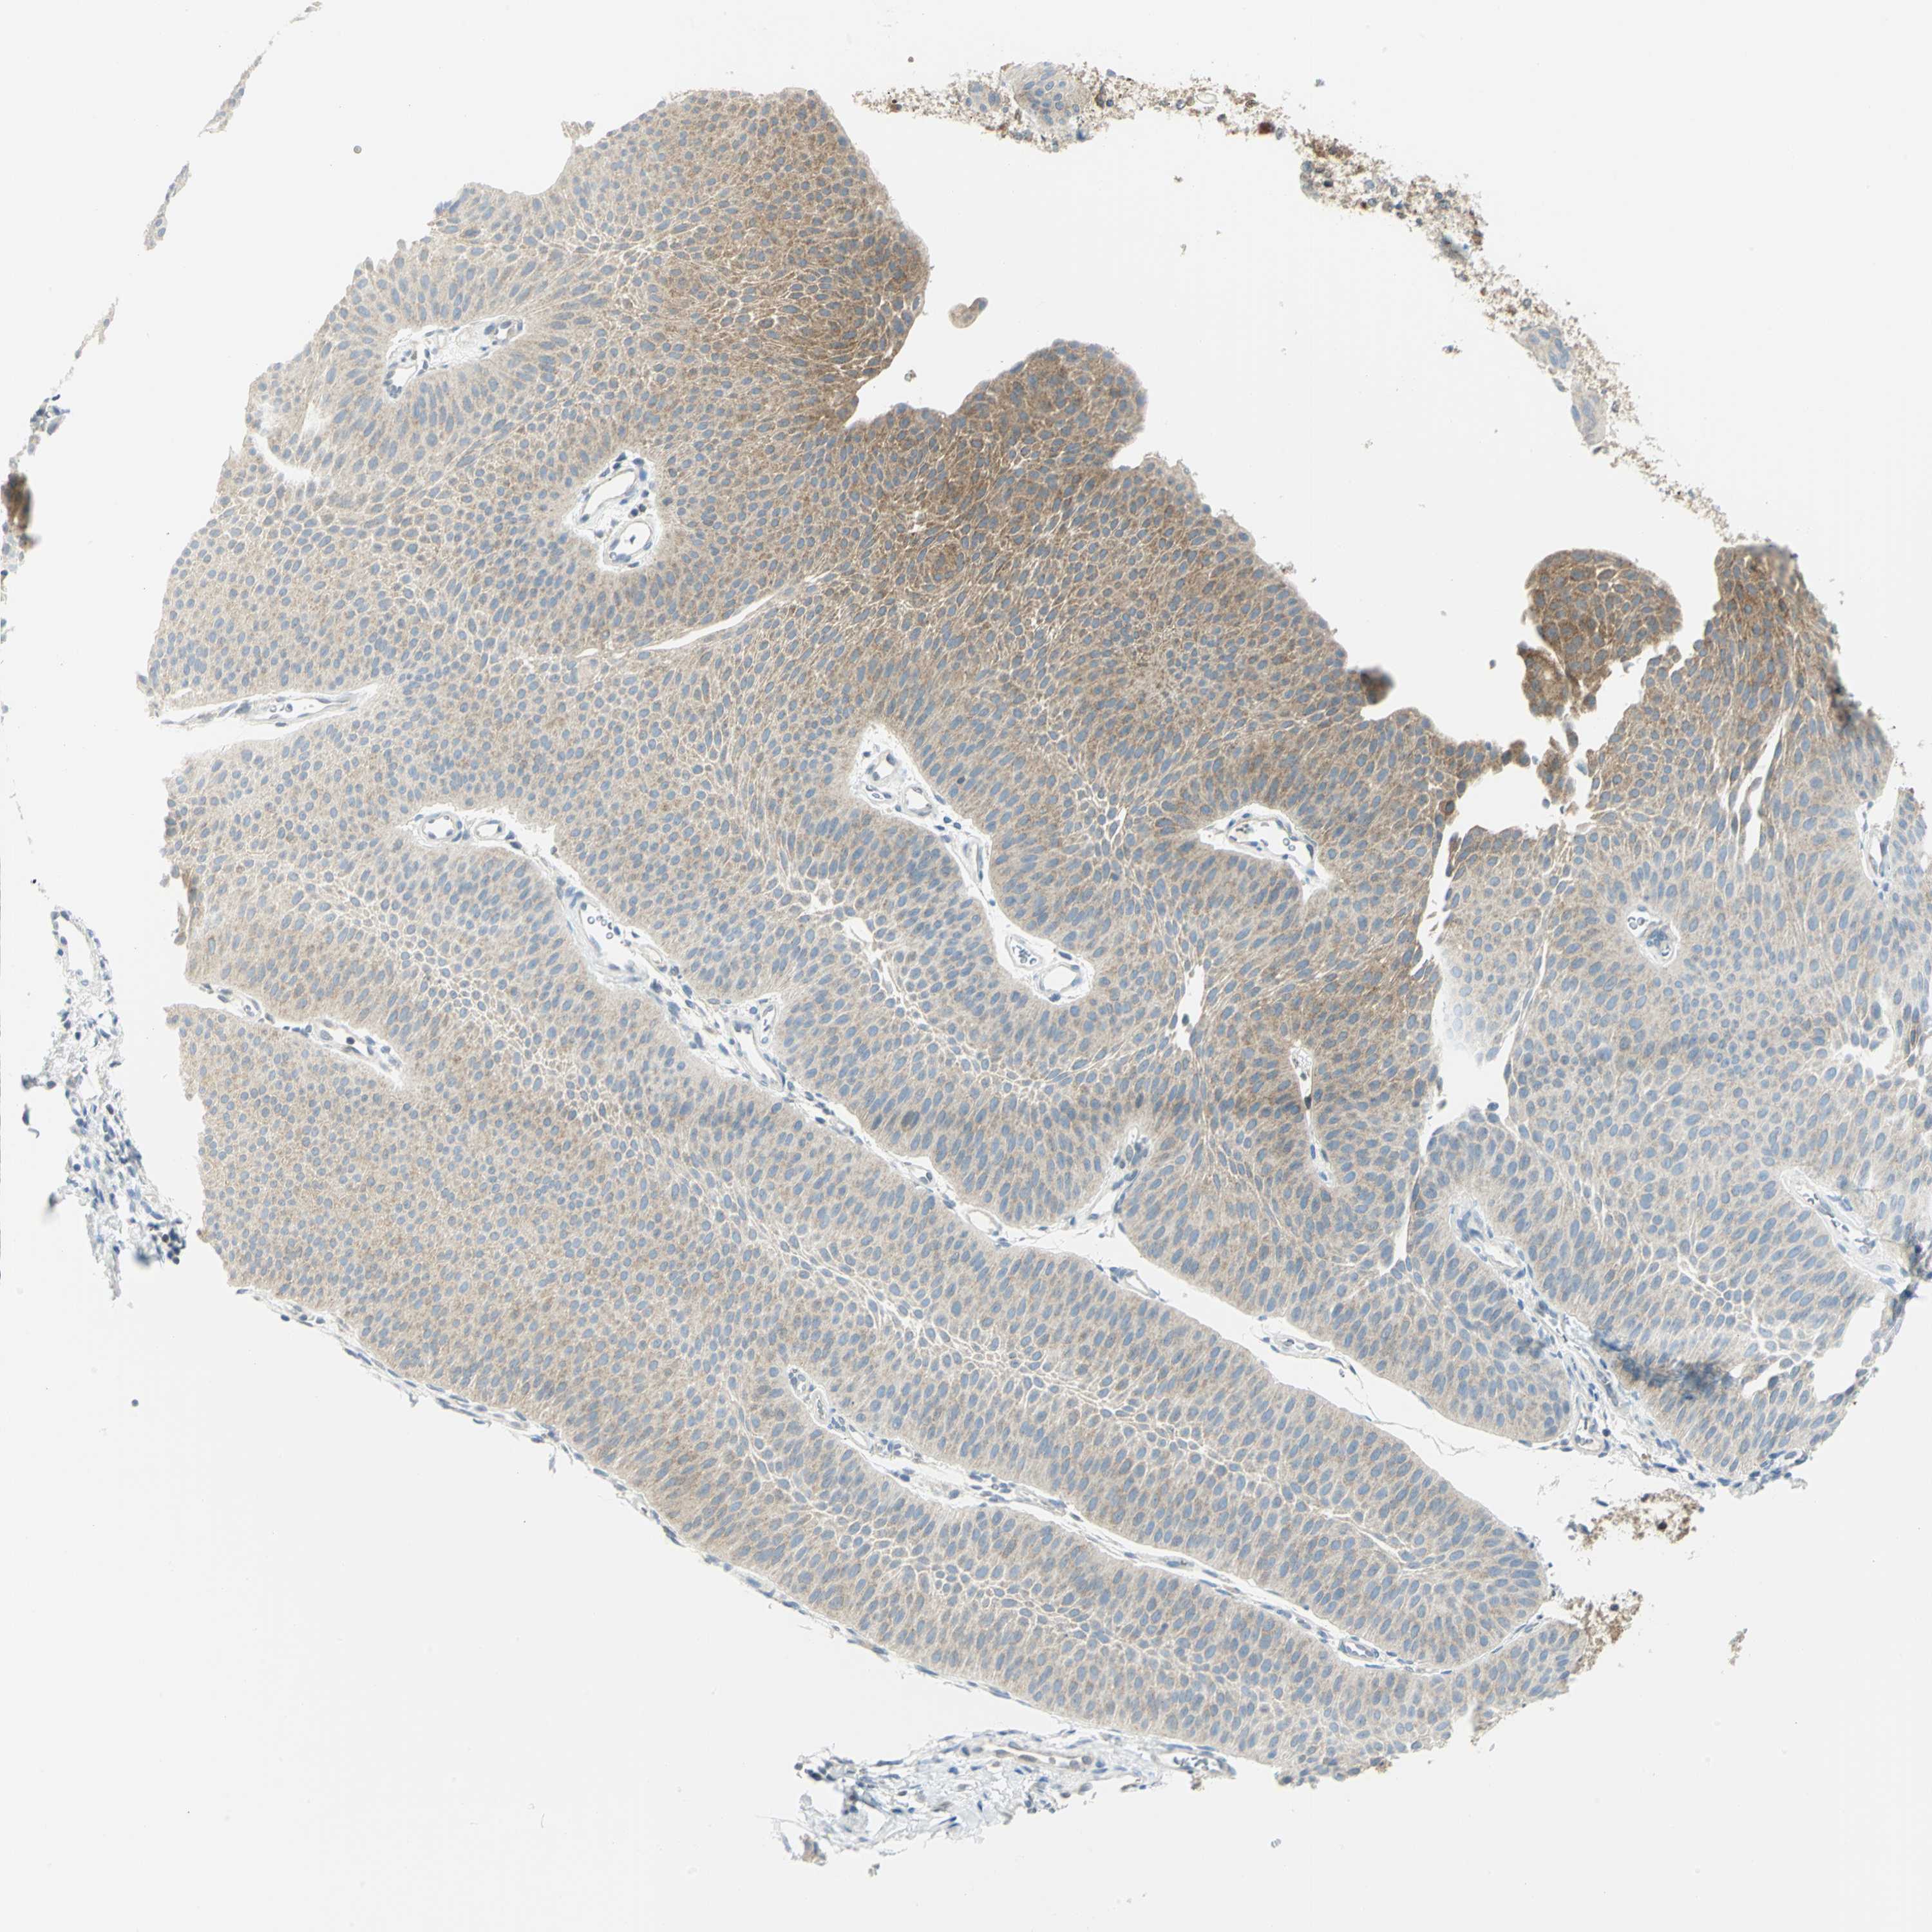

UROTHELIAL CANCER - Protein expressioni

A mouse-over function shows sample information and annotation data. Click on an image to view it in a full screen mode. Samples can be filtered based on level of antibody staining by selecting one or several of the following categories: high, medium, low and not detected. The assay and annotation is described here.

Antibody stainingi

Antibody staining in the annotated cell types in the current human tissue is reported as not detected, low, medium, or high, based on conventional immunohistochemistry profiling in selected tissues. This score is based on the combination of the staining intensity and fraction of stained cells.

Each image is clickable and will lead to virtual microscopy that enables deeper exploration of all samples and also displays staining intensity scores, fraction scores and subcellular localization as well as patient and tissue information for each sample.

Antibody HPA004177

Antibody CAB006252

Urothelial carcinoma, High grade

Urothelial carcinoma, Low grade